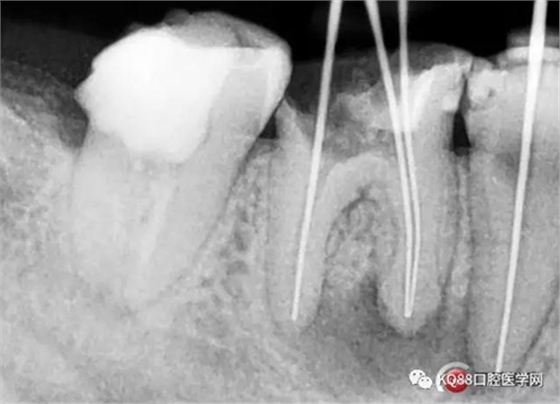

兩牙確定工作長度